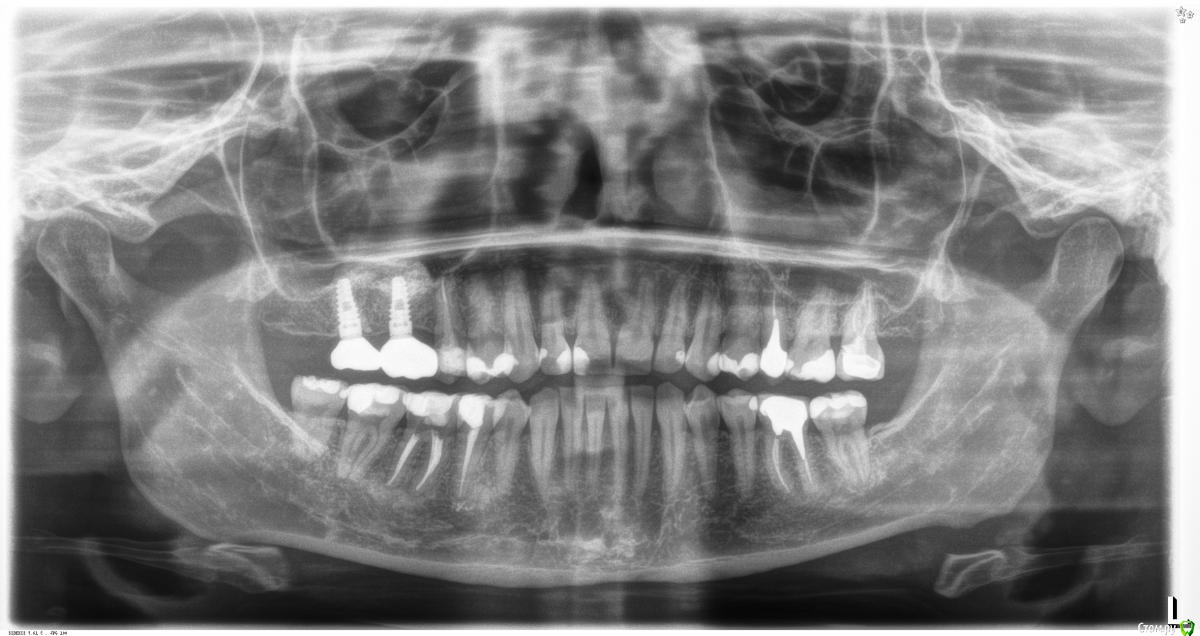

St. Опубликовано 13 июля, 2016 Автор Поделиться Опубликовано 13 июля, 2016 Асимптоматический периодонтит 35з. И случайная находка - трехканальный 34. Даж не знаю, хотела бы я такой полечить или нет) 1 Ссылка на комментарий